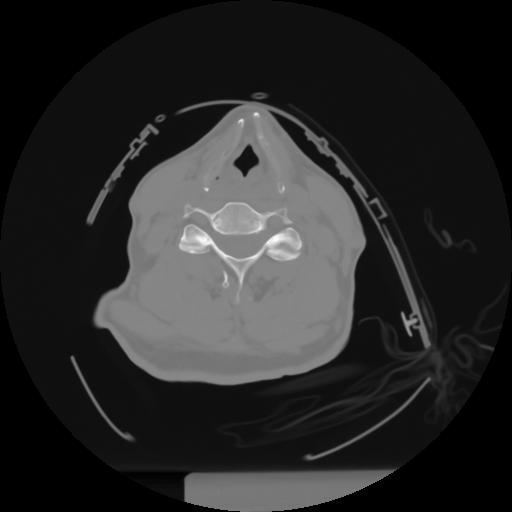

10 P.BLANDAS,,Axial,2.0,P.BLANDAS,,